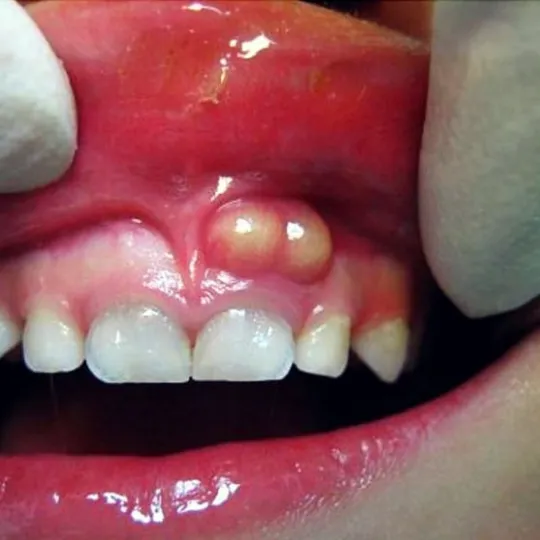

Inflammation of the gums or a tooth abscess

Once the bacteria reach your pulp, they can spread deeper into your gums or jawbone. Your gums may begin to swell, and you may notice a pimple-like bump on your gums.